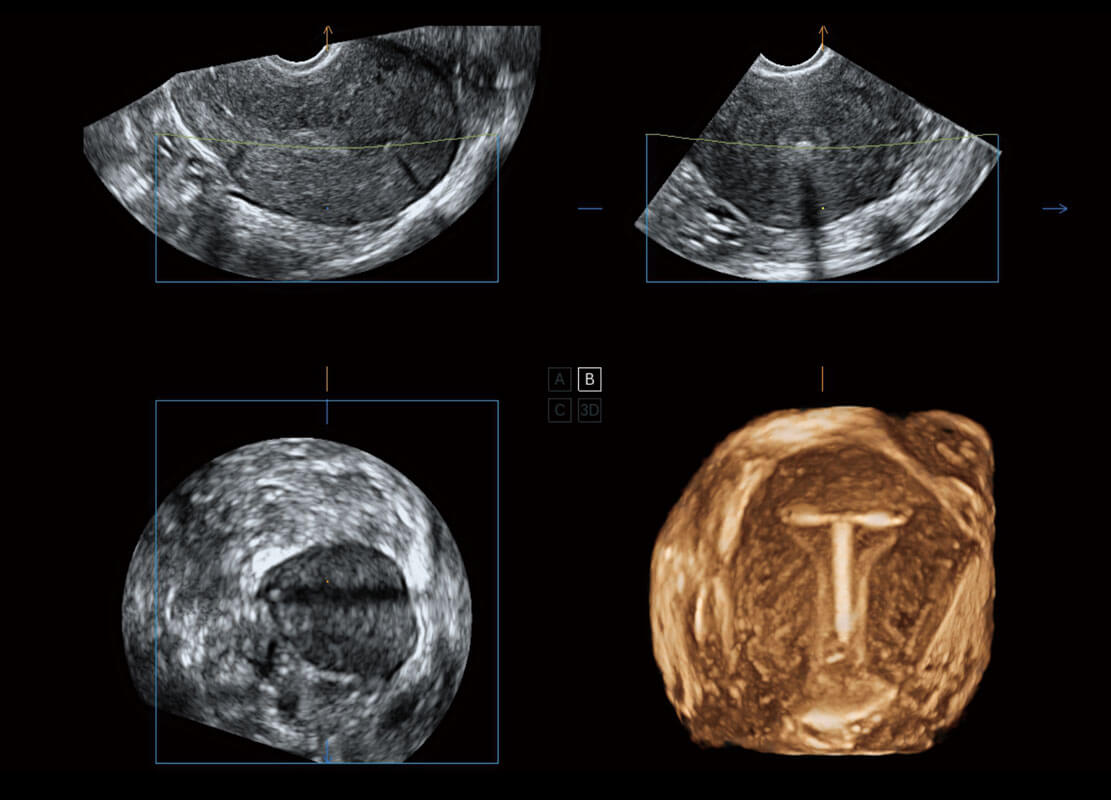

• 腔内三维-宫内节育器

盆底超声

P60为盆底超声检查提供应用方案,多种腔内及腹部容积探头提供从二维、三维到四维的优异图像品质,实时快速三维容积数据获取,专业的测量工具包等人性化设计,为超声医生诊断提供有力保障。

Lev.Hiat A-r: 16.33 cm2

Lev.Hiat H-r: 53.70 mm

Lev.Hiat W-r: 43.96 mm

Lt-LUG-r: 24.16 mm

Rt-LUG-r: 19.94 mm

S-Pelvic

能够简化盆底检查的操作流程,可在二维模式及三维成像模式下实现一键自动提取出标准切面、自动识别当前切面、自动测量,提升盆底检查的高效性,同时也能让青年医生快捷的获得准确的检查结果。